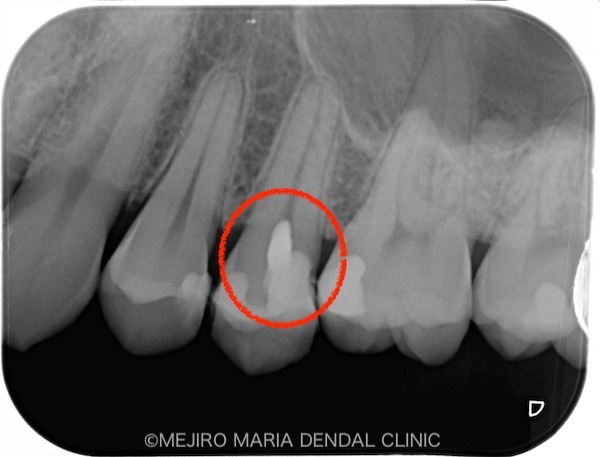

による歯髄保存症例(精密根管治療)_レントゲン_治療後1.jpg)

による歯髄保存症例(精密根管治療)_レントゲン_治療後2.jpg)

術後2週間経過した時点で、歯髄の反応が正常であることを確認しました。今後は、セラミックインレーを装着する予定です。